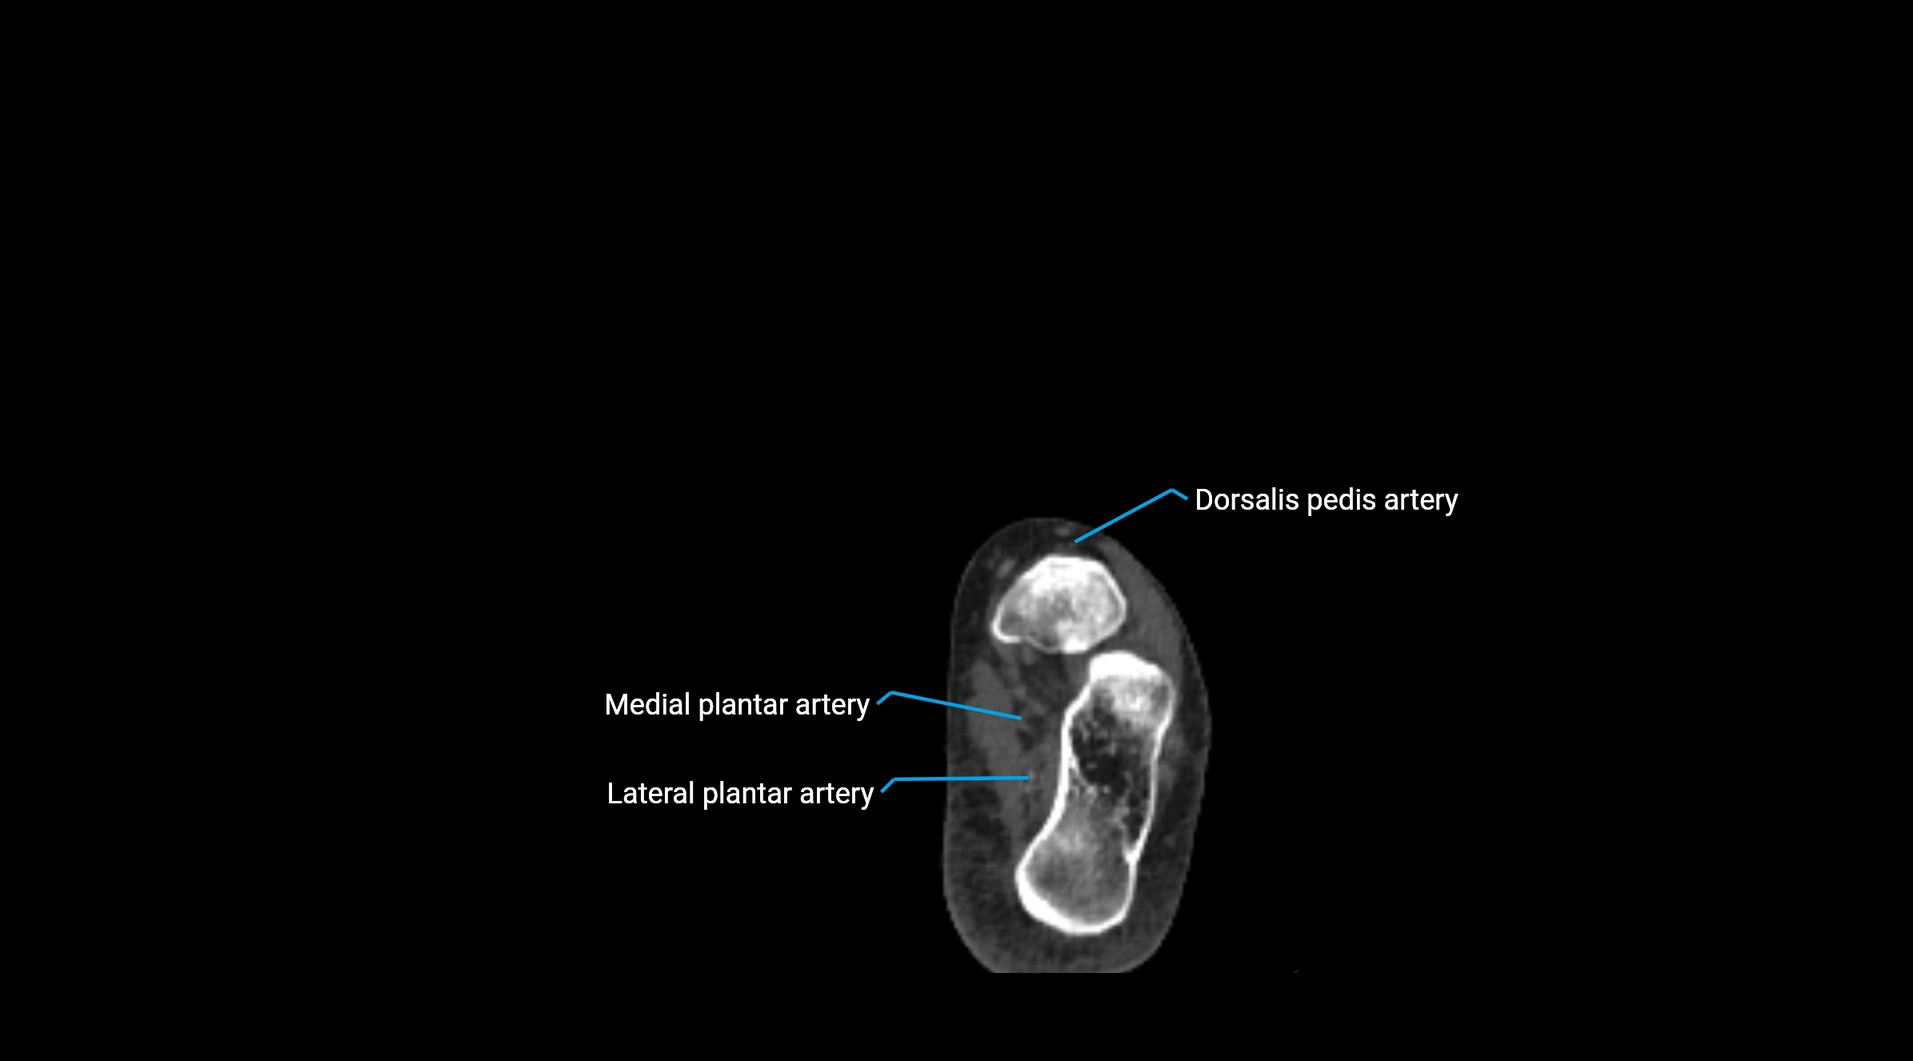

Contrast-enhanced CT (CTA):

• Gold standard for abdominal aortic imaging

• Provides excellent detail of lumen, wall, aneurysm, thrombus, and branch vessels

• Multiplanar and 3D reconstructions help in aneurysm measurement, stent graft planning, and dissection evaluation

• Detects acute rupture, traumatic injury, or occlusion with high sensitivity